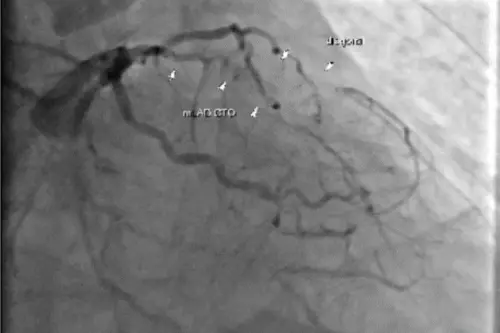

男心血管塞住3條倒下去!迷你人工心臟搶命 小傷口植入3天可下床

一名年約70歲男性日前發生急性心肌梗塞,經家人趕緊送醫後,醫療團隊檢查發現他的心臟血管有3條嚴重阻塞,必須進行心臟繞道手術搶命,擔心他過不去,於是使用俗...